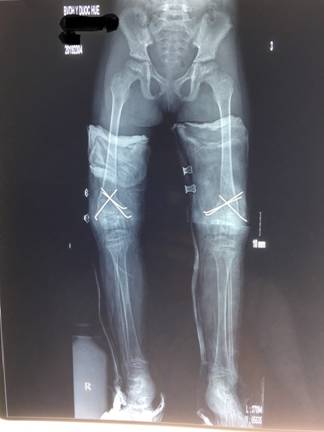

X quang sau mổ

Sau phẫu thuật, hậu phẫu tiến triển tốt, được chụp X-quang đánh giá sau mổ và bệnh nhi đã được ra viện sau 1 tuần. Sau mổ bệnh nhân được bó bột Đùi-cẳn bàn chân tăng cường và sẽ được tái khám theo lịch hẹn để tập PHCN và đi lại.